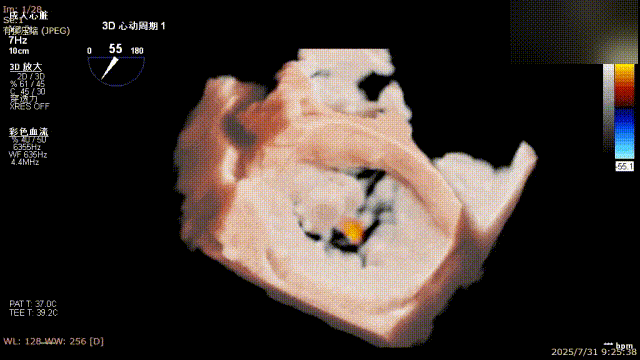

三维评估

二尖瓣P1脱垂偏心性返流

术前影像